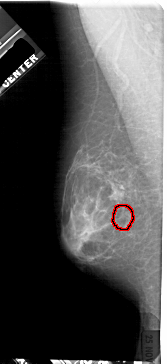

A_1931_1.LEFT_CC

LEFT_CC LINES 4981 PIXELS_PER_LINE 2311 BITS_PER_PIXEL 12 RESOLUTION 43.5 OVERLAY

FILE: A_1931_1.LEFT_CC.OVERLAY

TOTAL_ABNORMALITIES 1

ABNORMALITY 1

LESION_TYPE MASS SHAPE IRREGULAR MARGINS ILL_DEFINED

ASSESSMENT 4

SUBTLETY 4

PATHOLOGY MALIGNANT

TOTAL_OUTLINES 1

BOUNDARY